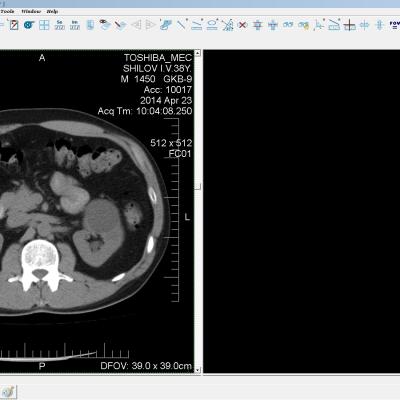

Здравствуйте. У меня киста левой почки. Из заключения: левая почка увеличена, деформирована за счёт наличия в среднем сегменте округлого жидкостного +6, +15 HU образования 66х53 мм, деформирует, поддавливает чаше-лоханочную систему. Сосудистые ножки структурные. В урологии мне сперва предложили лапароскопию, когда я лёг на операцию - изменили на полостную в связи со сложностью. Потом сказали что шансов вырезать кисту без почки практически нет. Даже если кисту удалить чудесным способом, то почка всё равно сложится и не будет работать. В итоге операцию отменили. Скажите, пожалуйста, есть ли современный метод удалить кисту и сохранить почку в моём случае? Томография почки в приложениях. Заранее благодарю.

Эту кисту можно просто пропунктировать, аспирировать и склерозировать - под местной анестезией. Ничего сверхестетственного не определяется по данным КТ. Можете написать мне на почту. aristova-tatyana@mail.ru